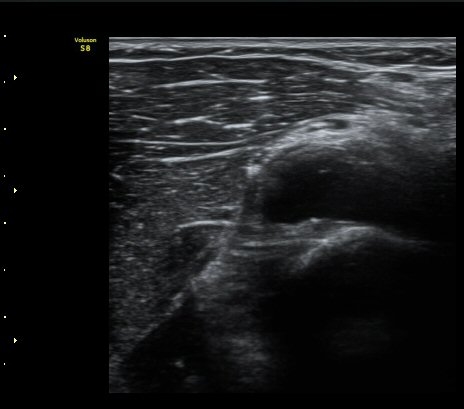

ŽÃËÀÚ¸¦ Á» ´õ ¸»´ÜÀ¸·Î À̵¿ÇÏ´Ï ³¶Á¾Àº ´õ Å©°Ô °üÂûµÈ´Ù(±×¸² 3, 4).